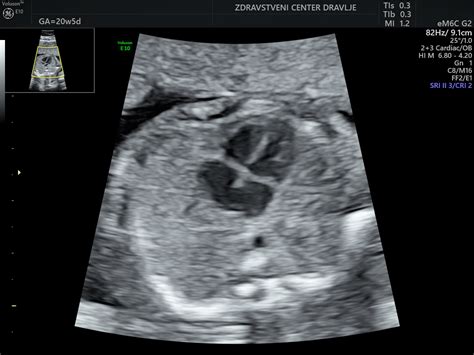

V 16. tednu nosečnosti je pomembno, da se naročite na naslednje preglede. Ultrazvočni pregled morfologije ploda, ki običajno poteka okoli 20. tedna, je ključen za oceno razvoja otroka. Prav tako se v tem obdobju izvajajo laboratorijske analize krvi in urina, vključno s testom na nosečniško sladkorno bolezen.